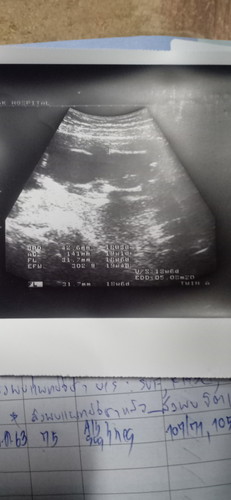

แบบนี้ดูเพศได้ไหมค่ะ ญ/ช ดูไม่เป็นจริงๆค่ะขอคำแนะนำหน่อย